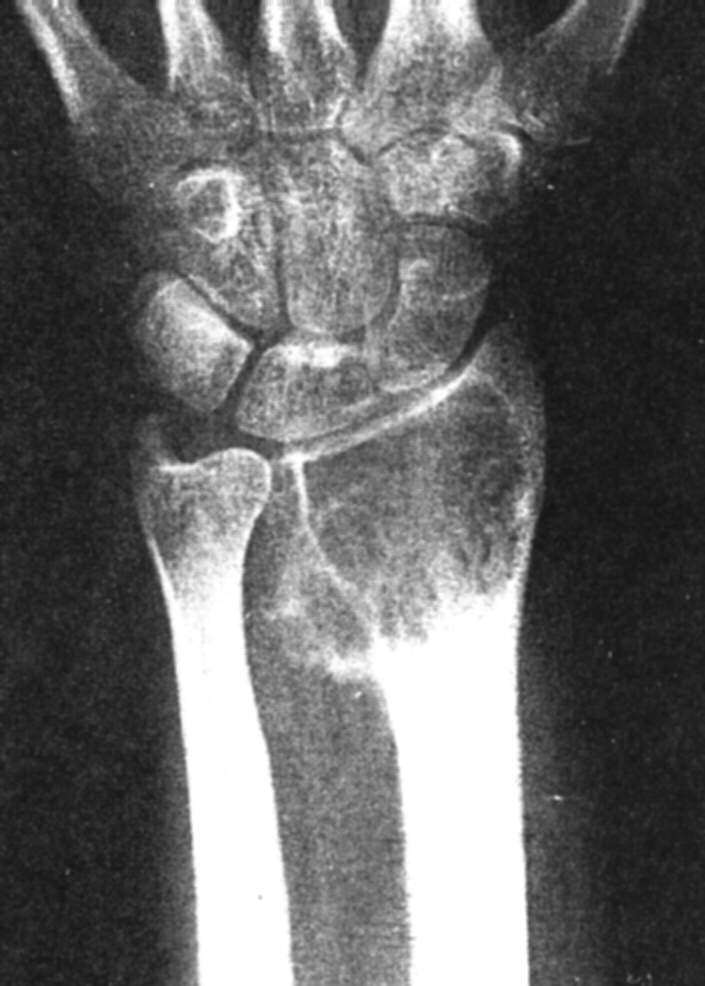

This is a rare malignant tumour, and is found often in the tibia, and occasionally in the other long bones. Most patients are young adults who present with long term pain, particularly over the tibia, with mild swelling or local bony deformity. Clinically there is thickening and tenderness along the subcutaneous boarder of the tibia.

Imaging

This shows on X-ray as multiple sharply circumscribed lucent defects of different sizes, with sclerotic bone between these lucency’s.